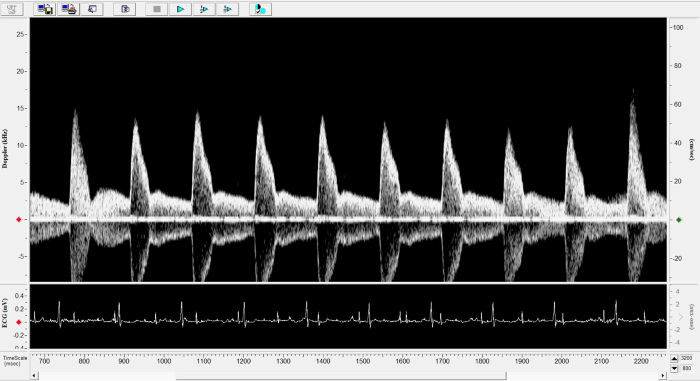

Imaging gallery - Doppler Flow Velocity System

Carotid Image. Image Credit: Scintica Instrumentation Inc.